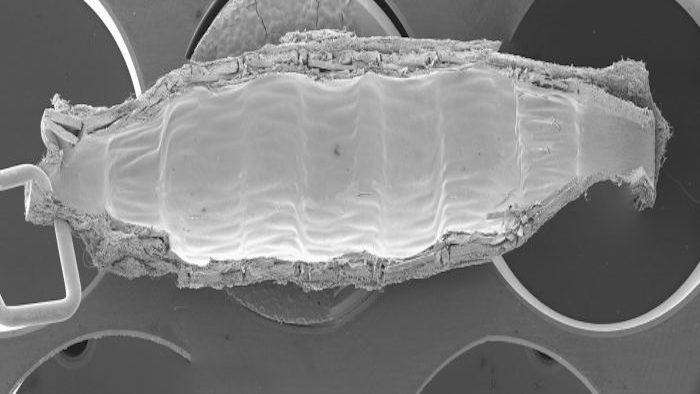

As a vital part of the Institute’s overall cardiovascular research team, THI’s cardiovascular pathologists work to provide researchers with critical information they need to progress their studies forward.